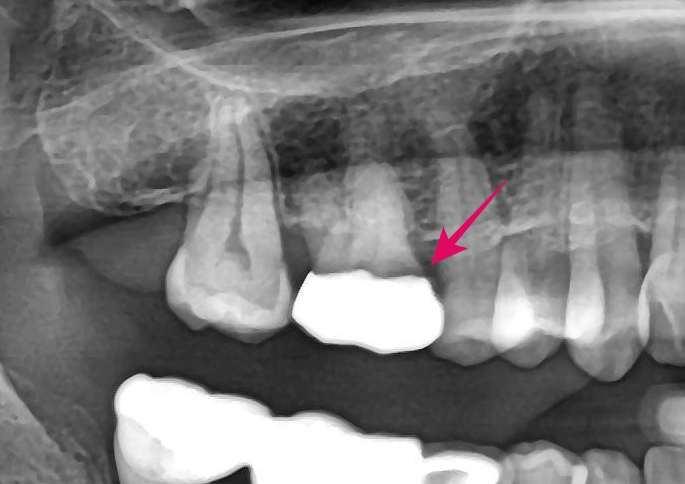

▲ 엑스레이 사진: 화살표가 가리키는 부위에 보철물과 치아 사이의 틈(Gap)이 관찰됩니다.

엑스레이를 촬영하여 정밀 진단한 결과, 화살표가 가리키는 부위에서 금니와 치아의 경계 부위(마진)가 딱 맞지 않고 붕 떠 있는 것이 확인되었습니다. 이 '틈(Gap)'이 가장 위험합니다. 보철물을 붙였던 접착제가 침에 의해 녹아 사라지면, 그 미세한 틈으로 음식물과 세균이 끊임없이 침투하게 됩니다.